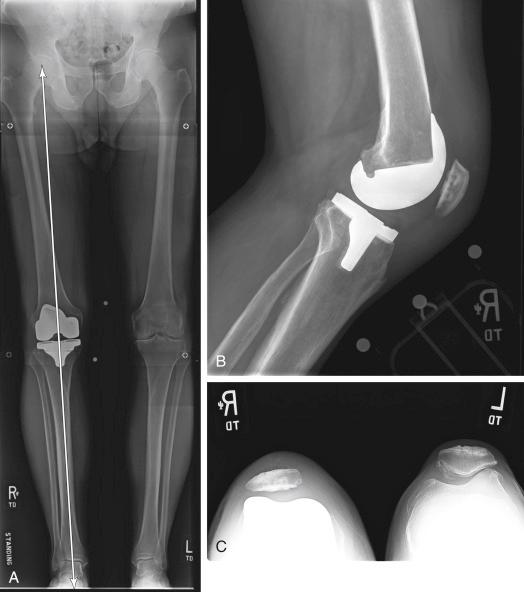

FIGURE 14.1, A, Hip-to-ankle radiograph demonstrates acceptable limb alignment (arrow) . B, Lateral radiograph shows appropriately positioned and sized components. C, Patellar view demonstrates a mild tilt but shows no evidence of overstuffing or malpositioning.